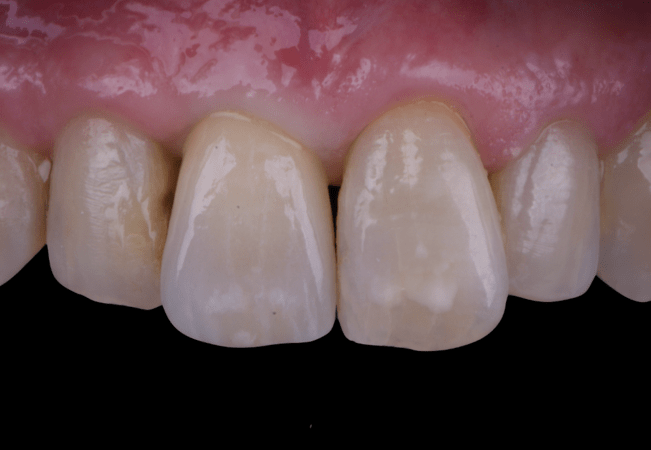

After an appropriate healing period, the definitive prosthesis was planned and delivered. A screw-retained zirconia crown was fabricated to ensure long-term durability, optimal esthetics, and retrievability. Zirconia was selected for its mechanical strength and excellent esthetic properties, blending seamlessly with the adjacent natural dentition in both form and color.

The final crown was designed to maintain the gingival architecture that had been shaped by the provisional. Special attention was paid to the emergence profile, contact points, and translucency to achieve harmony with the patient’s smile. The definitive restoration provided functional stability and esthetic integration, fulfilling the patient’s expectations for a fixed and natural solution.

This case demonstrates the benefits of combining immediate implant placement with simultaneous guided bone regeneration and connective tissue grafting in a high-esthetic area. The use of the N1 system and the “one abutment one time” protocol facilitated predictable healing and minimized disturbance of peri-implant tissues. Immediate provisionalization contributed significantly to soft tissue shaping and patient satisfaction throughout the process.

Key learnings include the importance of careful planning when treating cases with buccal bone wall resorption in the anterior maxilla. The integration of advanced biomaterials, such as creos™ xenogain™ and membranes, along with soft tissue augmentation techniques, ensures stability of both hard and soft tissues. This case reinforces that implant treatment in esthetic zones can achieve excellent outcomes when biological and prosthetic principles are applied in harmony.